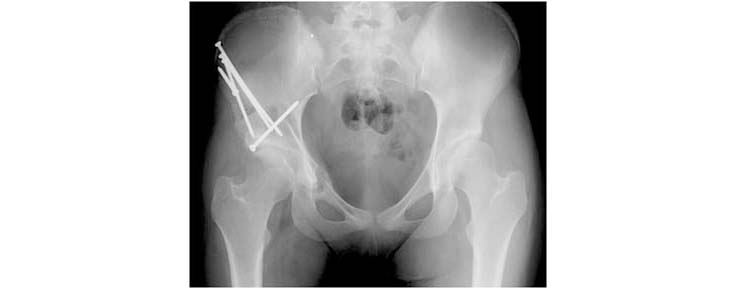

9.This is the final radiograph demonstrating the correction of the deformity and the position of the hip screws used to stabilize the cut bone fragment which contains the hip socket.

The procedure involves the cutting of the pelvis at specific points with complete mobilization of the hip socket. The socket is then fixed in place with screws. Post-surgical weightbearing is restricted for at least 6 weeks and sometimes longer until there is evidence of healing on the x-rays.

7.Once the optimal position is achieved the fragment containing the hip socket (arrow) is held in place with smooth wires from the top of the ilium bone.

8.Bone graft obtained during the bone cuts is the used to bridge the triangular space created by the configuration. This bone graft remodels over time to form a sturdy bone bridge across the cut bone.